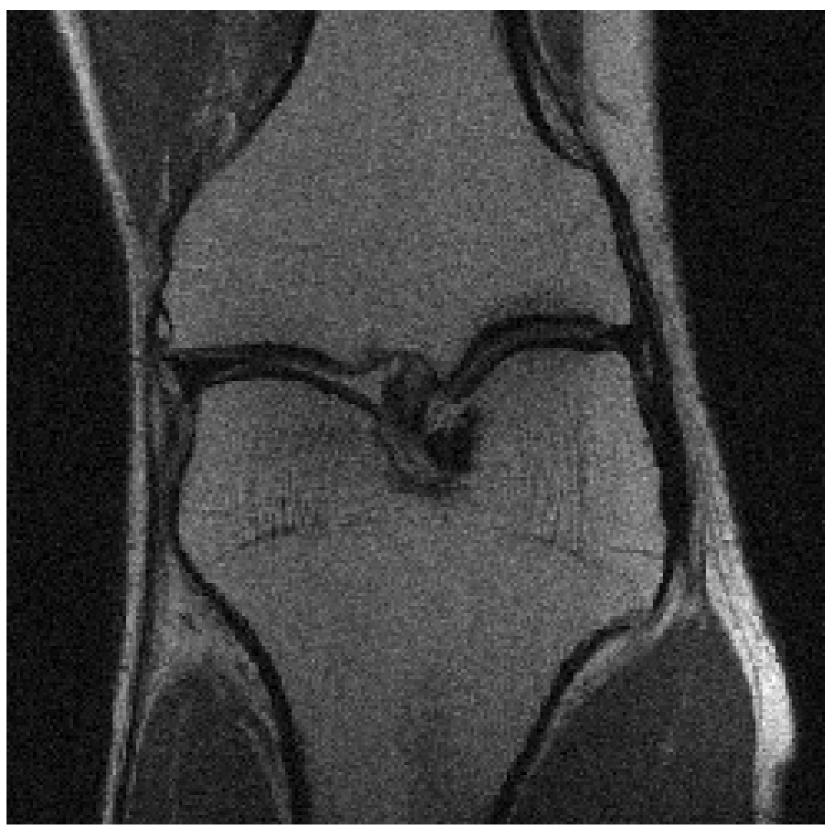

We evaluated our models on three data sets: the validation set as in Zbontar et al. (2018), and the test and challenge sets through the fastMRI website. A summary of these evaluations can be found in table 1111Results on the challenge data set will be added once publicly available.. To assess image quality more closely, we show some exemplary reconstructions from each model in figure 1.

Figure 1: Example reconstructions. The reconstructions visually improve the ground truth images, suggesting a strong prior.